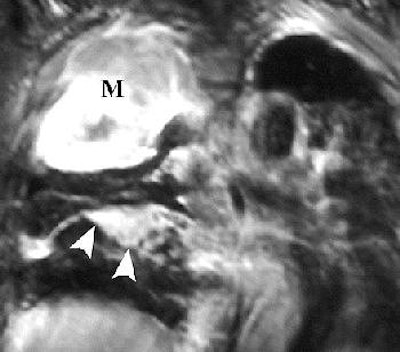

![]() |

R imaging evaluation of MPM in 63-year-old man. Coronal (top) and contrast-enhanced fat-saturated (below) T1-weighted MR images show a large, enhancing right apical mass with invasion of chest wall (black arrows, top). An enhancing right major fissure is also seen (white arrowheads, below). Figure 16, Wang ZJ, Reddy GP, et al, "Malignant Pleural Mesothelioma: Evaluation with CT, MR Imaging, and PET" (RadioGraphics 2004; 24: 105-119).

Investigators from the University of California, San Francisco came to similar conclusions, advocating MR imaging in patients with potentially resectable disease.

"The excellent contrast resolution of MR imaging can allow improved detection of tumor extension.... Loss of fat planes, extension into mediastinal fat, and tumoral encasement of more than 50% ... are some of the features that suggest tumor extension," wrote Dr. Zhen Wang and colleagues in an educational exhibit for RadioGraphics (January-February 2004, Vol. 24:1, pp. 105-119).